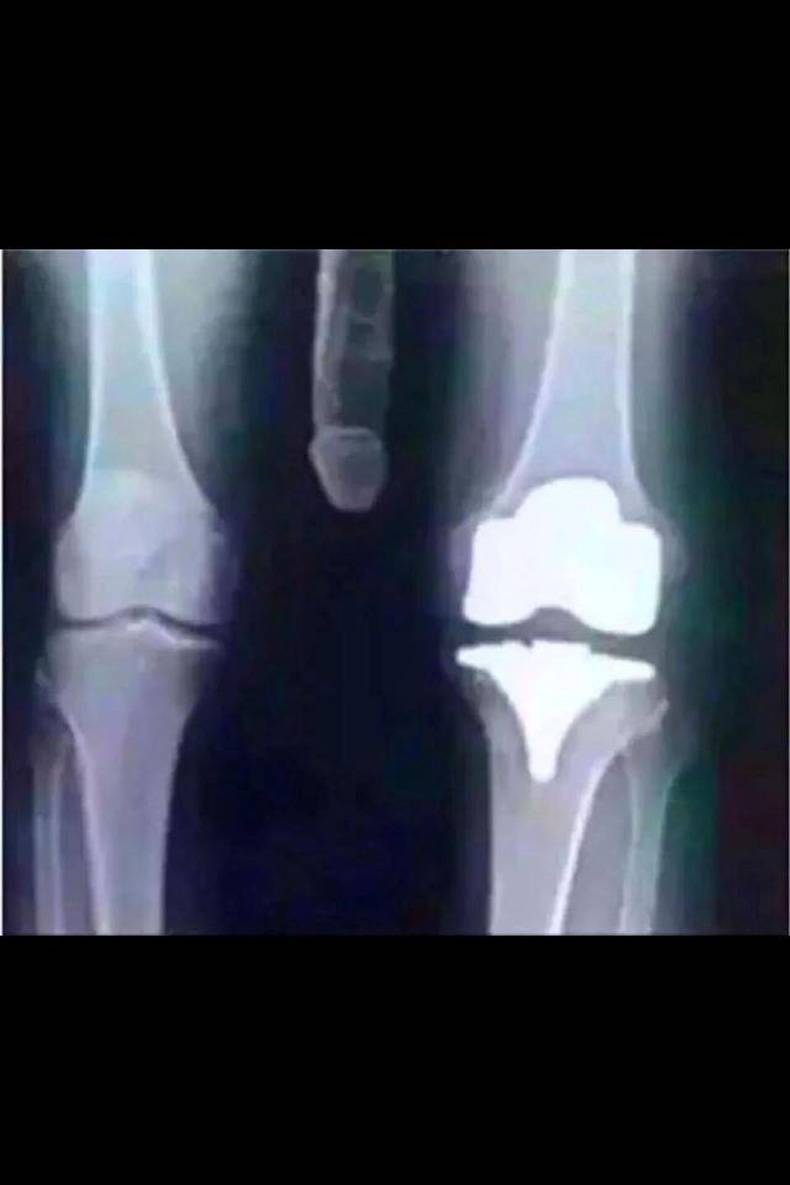

'k Zal hier eens de eerste pagina van mijn medisch dossier van liefst drie universitaire ziekenhuizen, waarvan één in het buitenland, onthullen:

Bijgevoegde miniaturen

Klik op de afbeelding voor een grotere versie

Naam:  pic_112_clean_790.jpg‎

Bekeken: 87

Grootte:  38,3 KB

ID: 101074

Citaat:

Oorspronkelijk geplaatst door De schoofzak Bekijk bericht

Yep, alweer verkeerd.

Schoofzak, doe dat nooit meer.

Daar heeft niemand zaken mee.